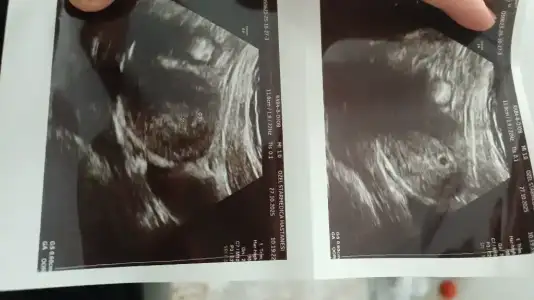

Gözünüz aydın olsun cnm kese kaç mm cikti kaç haftalıkkızlar yaa kese gördük 2 hafta sonraya çağırdı kalp atışı için bana çok uzun geldikalp atışından sonra doktorlar nasıl yol izliyo bir daha ne zaman çağırıyo

sağol canım teşekkür ederim doktor 5 haftalık dedi 8,5 mm çıktı ufacıkGözünüz aydın olsun cnm kese kaç mm cikti kaç haftalık

Ya benimkide 5 haftalık ama 6mm dedi bi benimki küçük sanırım ya 5+ kaçsın cnm ve kaçta gittinsağol canım teşekkür ederim doktor 5 haftalık dedi 8,5 mm çıktı ufacık![]()

ay çok güzell ufak falan değil bence her gün 1.1mm büyürmüş kese belki ben 5+4 falanımdır ondan 8,5mm çıkmıştır. doktor sağlıklı gayet iyi dediyse canını asla sıkma bana mesela kesem çok garip geldi yuvarlak falan değil belki çekim açısından da olabilirEvet var 6mm 5+1de gittim bir benim snki 6mm ya küçük inslh iyidir

Kızlar keseme bi bakar mısınız düzgün mü şekli falanay valla 5 haftalık dedi ama artısını söylemedi açıkçası heyecandan sormayı da unuttum